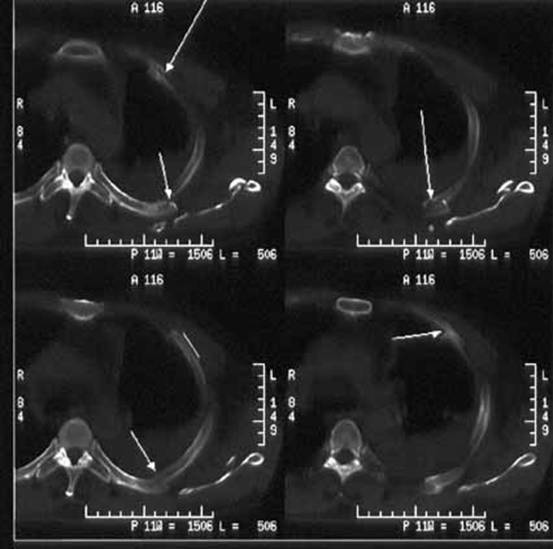

然而,对于细微骨折或者伴有出血的骨折需要用CT诊断了。CT也是发出X线,但与上述X线检查不同的,CT是断层成像,就切西瓜,一层一层的显示人体结构,避免了骨头前后重叠造成的影响。

而且CT的分辨率更高,能够显示更细微的骨裂。CT能从任意方向将图像进行二维和三维重建,换句话说,虽然它照的是断面,最后却能显示人的正面、侧面、背面、和斜面,还可以还原出一个立体的人。所以能更好评价骨折的严程度,并能清晰的显示脱落的碎骨片的位置和形态,为医生的治疗提供直观、准确的参考依据。因此CT已经越来越多地应用于骨折的诊断,特别在临床症状强烈提示骨折,但X光片上并未发现明显骨折时;或者X光片上发现了明显骨折,医生仍想确认是否还存在其他细微骨折时。